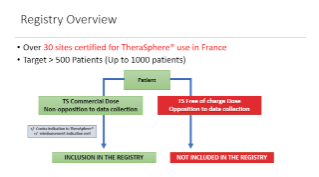

Personalised dosimetry in real life: the PROACTIF experience

Oct 08, 2020

External Link( 10.0 MB )

Prof. Thierry de Baere introduces the PROACTIF experience and focuses on personalised dosimetry